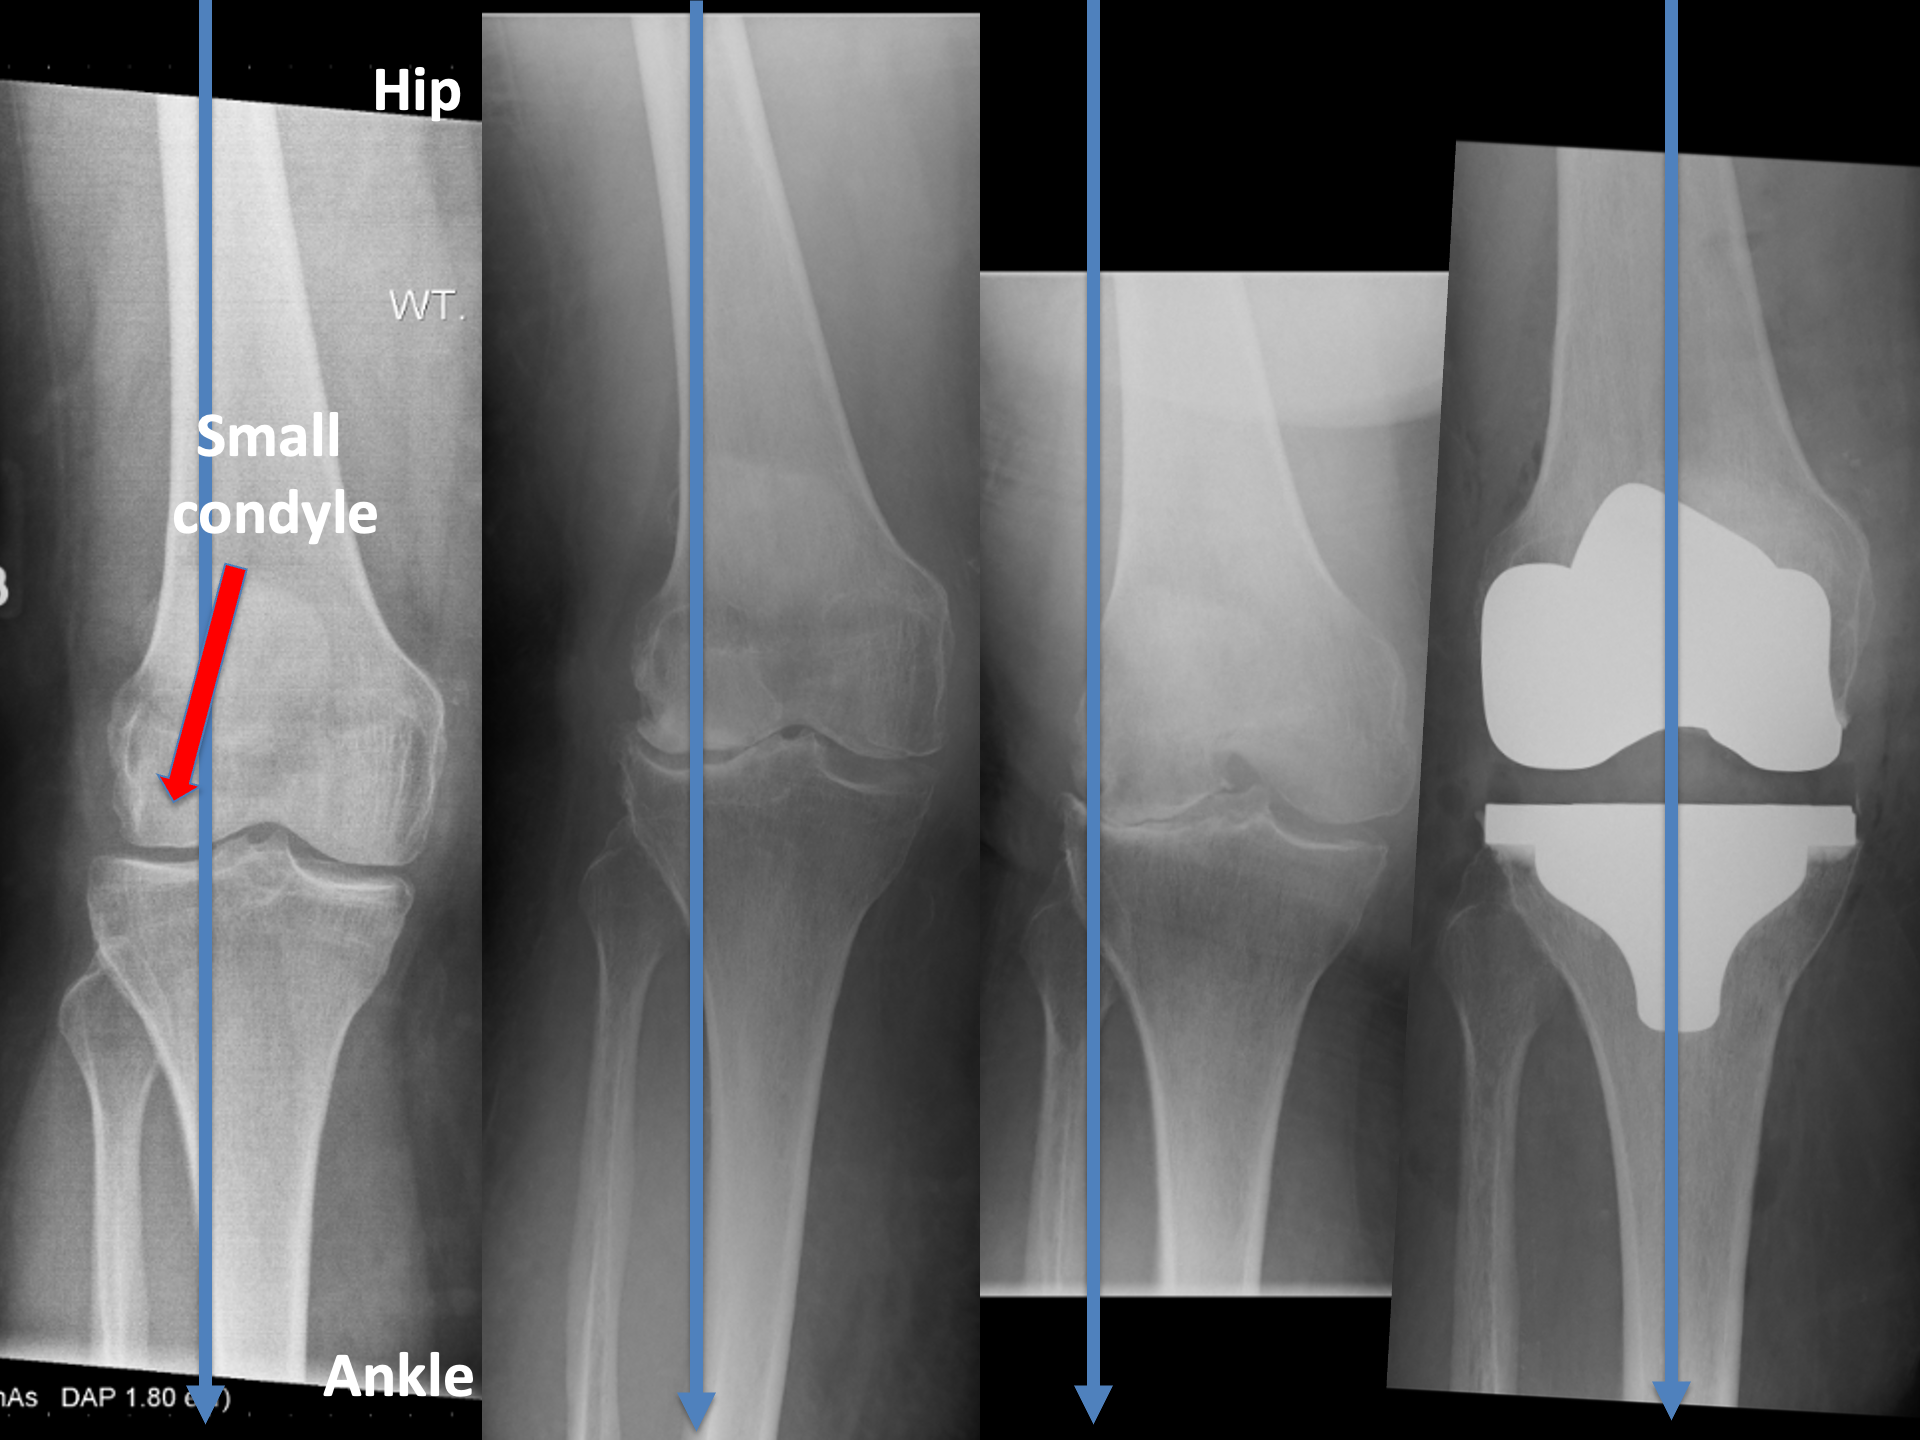

This level of deformity (see 3.)

That knee is not getting better.

AND is likely to get worse.

So, we got on with a RIGHT Total Knee Replacement.